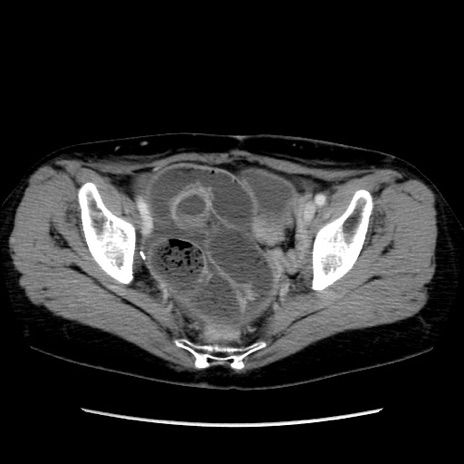

症例32(横断像)

【症例】40歳代 女性

【主訴】上腹部痛、嘔気・嘔吐

【現病歴】約9時間前頃から急に上腹部痛、嘔気、嘔吐が出現。改善しないため救急要請。

【既往歴】子宮頚癌(広汎子宮全摘術、放射線療法)、腸閉塞

【身体所見】腹部:平坦、軟、腸雑音亢進、上腹部を中心に腹部全体に圧痛あり。

【データ】WBC 8400、CRP 0.03